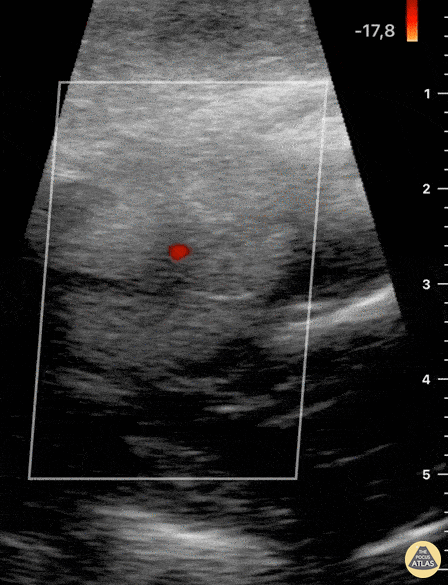

Soft Tissue - Blunt Neck Trauma (doppler)

Not your classic Blunt Neck Trauma: Doppler Color doppler shows an absence of flow in the deeper anechoic level and apparent indemnity in the glands vasculature. After the initial assessment, the patient remained hypertensive and tachycardia with HR of 120 bpm. Although there was no obvious worsening of airway status and no respiratory symptoms, the patient was referred to the regional centre for angio CT of the neck. This modality confirmed a right submandibular gland fragmentation with significant adjacent edema extending to the airway. There was airway midline deviation to the left and notable calibre reduction at the level of the hypopharynx. Dr. Felipe Urriola & Dra. Daniela Gallardo Emergency Unit, Puerto Aysen Hospital. Chilean Patagonia